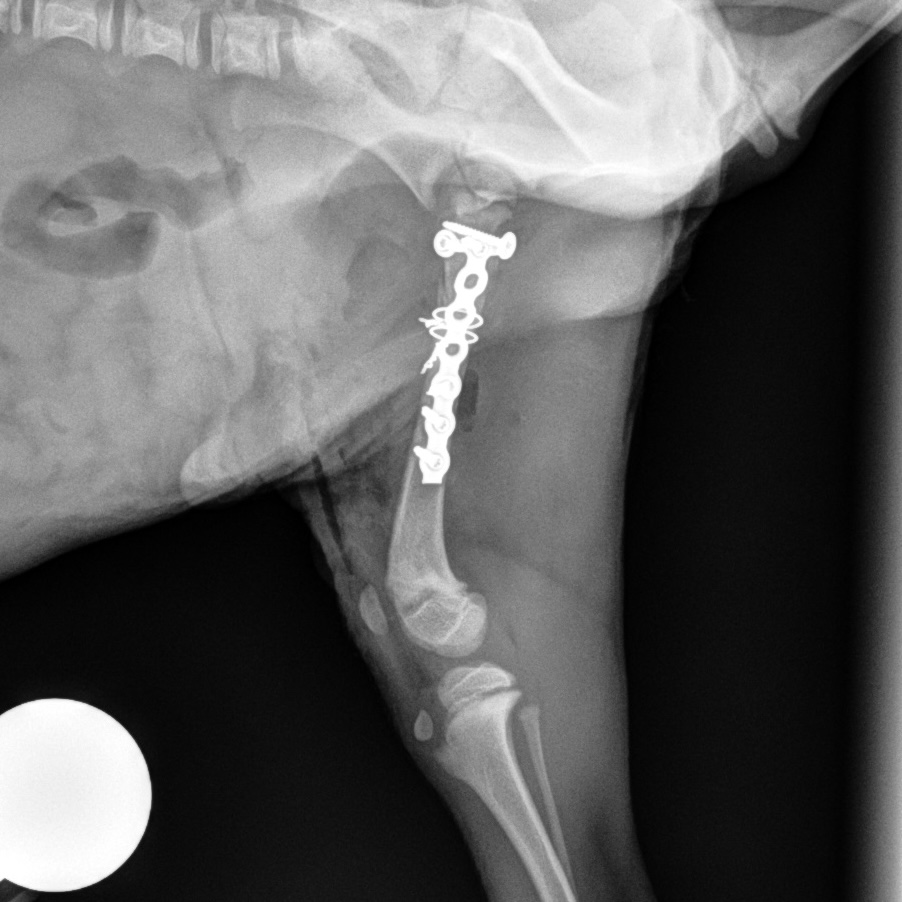

Femur Fracture Before

Femur Fracture After #1

Femur Fracture After #2